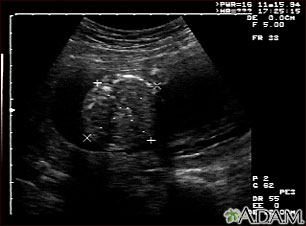

Ultrasonido normal a las 19 semanas de gestación. Muchos médicos prefieren tener las medidas fetales para verificar el tamaño del feto y buscar la presencia de cualquier anomalía. Este ultrasonido muestra las medidas abdominales de un feto; se aprecia un corte transversal del abdomen indicado por líneas punteadas y cruces.